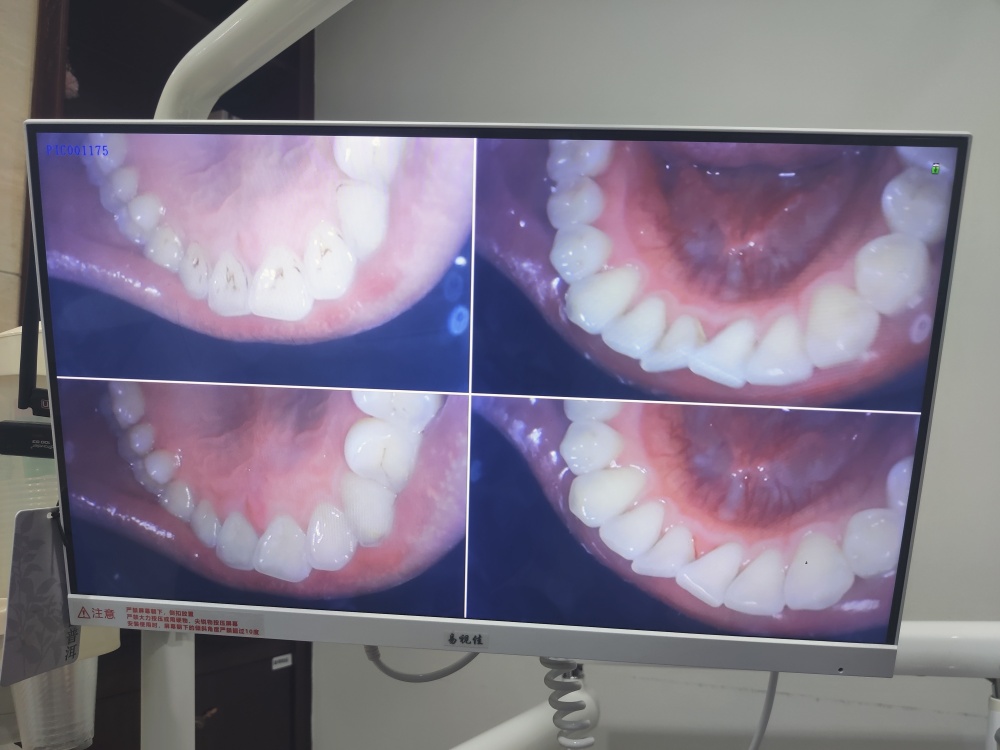

今天去爱齿尔口腔医院洗了个牙(美团黑金会员免费洗牙),顺便了解一下自己牙齿的健康状况,牙龈状态还不错,就是智齿问题有点烦,目前在预防智齿发炎,等钱包余额鼓鼓的再拔吧。我就担心有牙周炎最后牙龈萎缩,年纪轻轻牙齿就脱落了,就太惨了。还好我已经关注到牙齿健康的问题,还不算太晚。看别人牙龈萎缩最后牙齿掉没了,种牙就得20万,想想就可怕。而且食欲都受影响。吃啥,啥不香了!